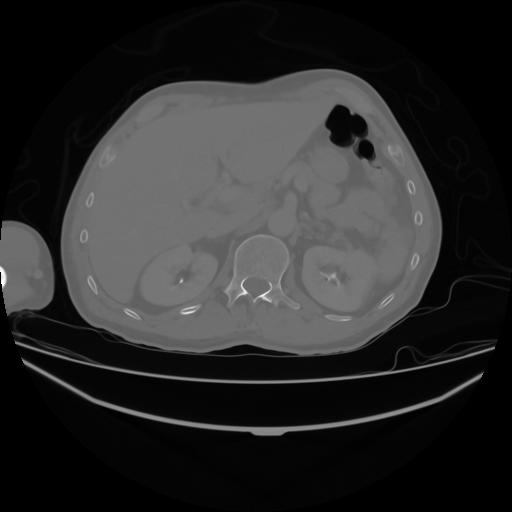

4 CUERPO,CE,Axial,3.0,CUERPO,,